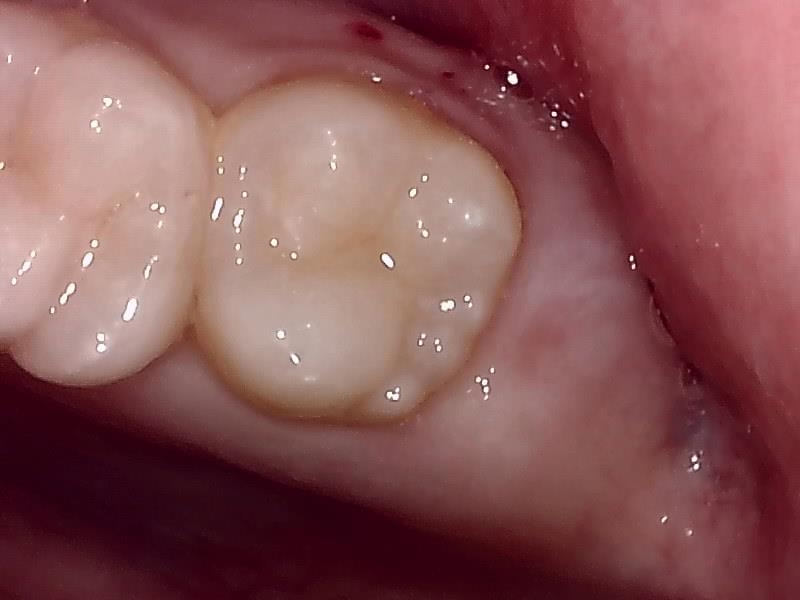

抜歯窩の写真 (左上)

縫合 (左上)

止血シーネで止血処置をする。(左上)

抜去歯

左下の抜歯窩

左下の縫合

治癒

当院では、傷口は最小限に、骨は極力削らずに行います。

骨が歯を覆っているケース以外は骨を削ることはありません。

親知らずのみにアプローチし歯を分割し最小限の傷口で取り出します。

歯肉を切開し、歯が見えるようにして、

周辺の骨を削らないように親知らずを分割し抜きやすくしていきます。

この抜歯法により術後の腫れ痛みが大幅に軽減されます。

抜歯後、経過良好です。